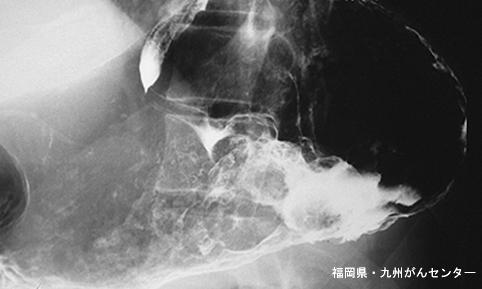

Posted by: Fukuoka Pref., Centro Kyushu de Curaciones de Cáncer

clasificación del pacienteTumor Epitelial Maligno/Adenocarcinoma

parte(separada por órganos)estómago(región)/cuerpo

método de exámenRayos X

clasificación ectoscópica de tumoresTipo 5(no clasificable)/

diámetro mayor del tumor40 -

grado de penetraciónss(a1)